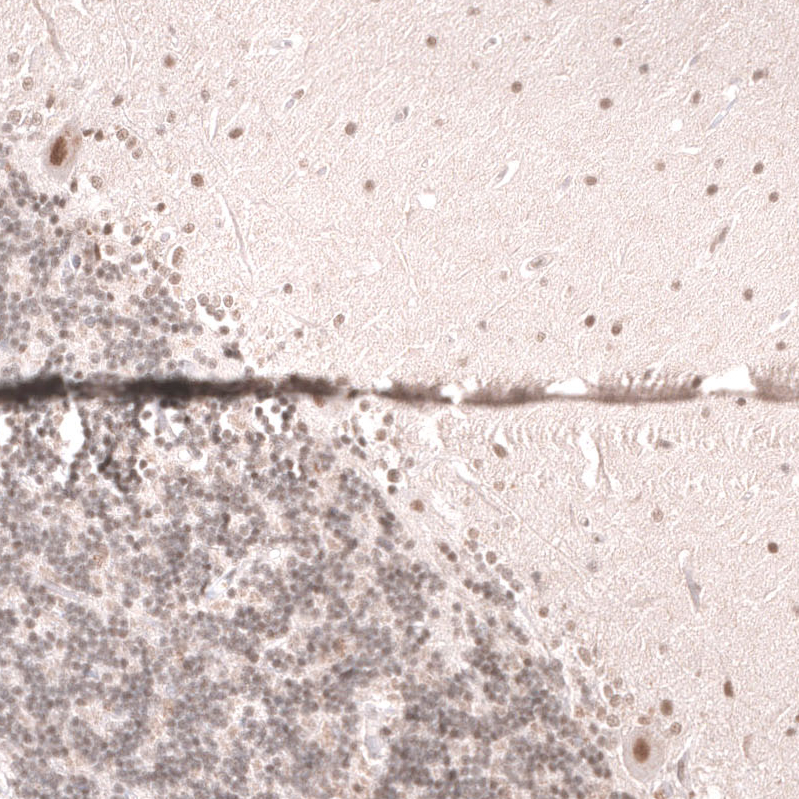

Immunohistochemical staining of human cerebral cortex shows strong nuclear positivity in neurons.